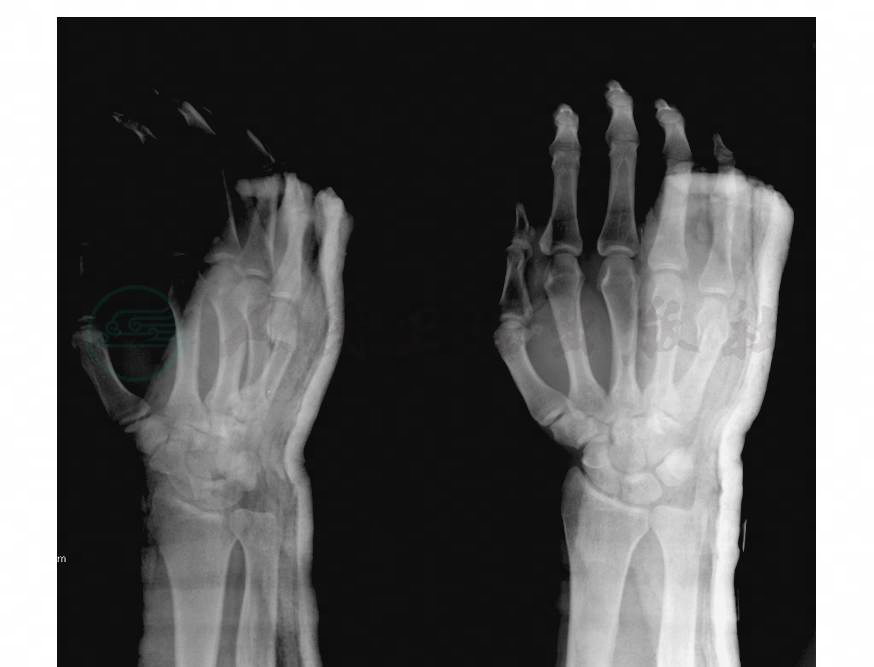

掌骨干骨折多见于第2~5掌骨,可为单根骨折或多根骨折(图8),多由诸如打击或挤压等直接暴力所致,多为横断或粉碎性骨折。若为扭转或传达暴力所致,多为螺旋或斜形骨折(图9)。由于骨间肌及屈指肌的牵拉,骨折常向背侧成角和侧方移位。单根的掌骨骨折移位较轻,而多根骨折则移位较甚,对骨间肌的损伤也比较严重。

图8 第2~5掌骨干骨折

图9 第3、4掌骨干骨折